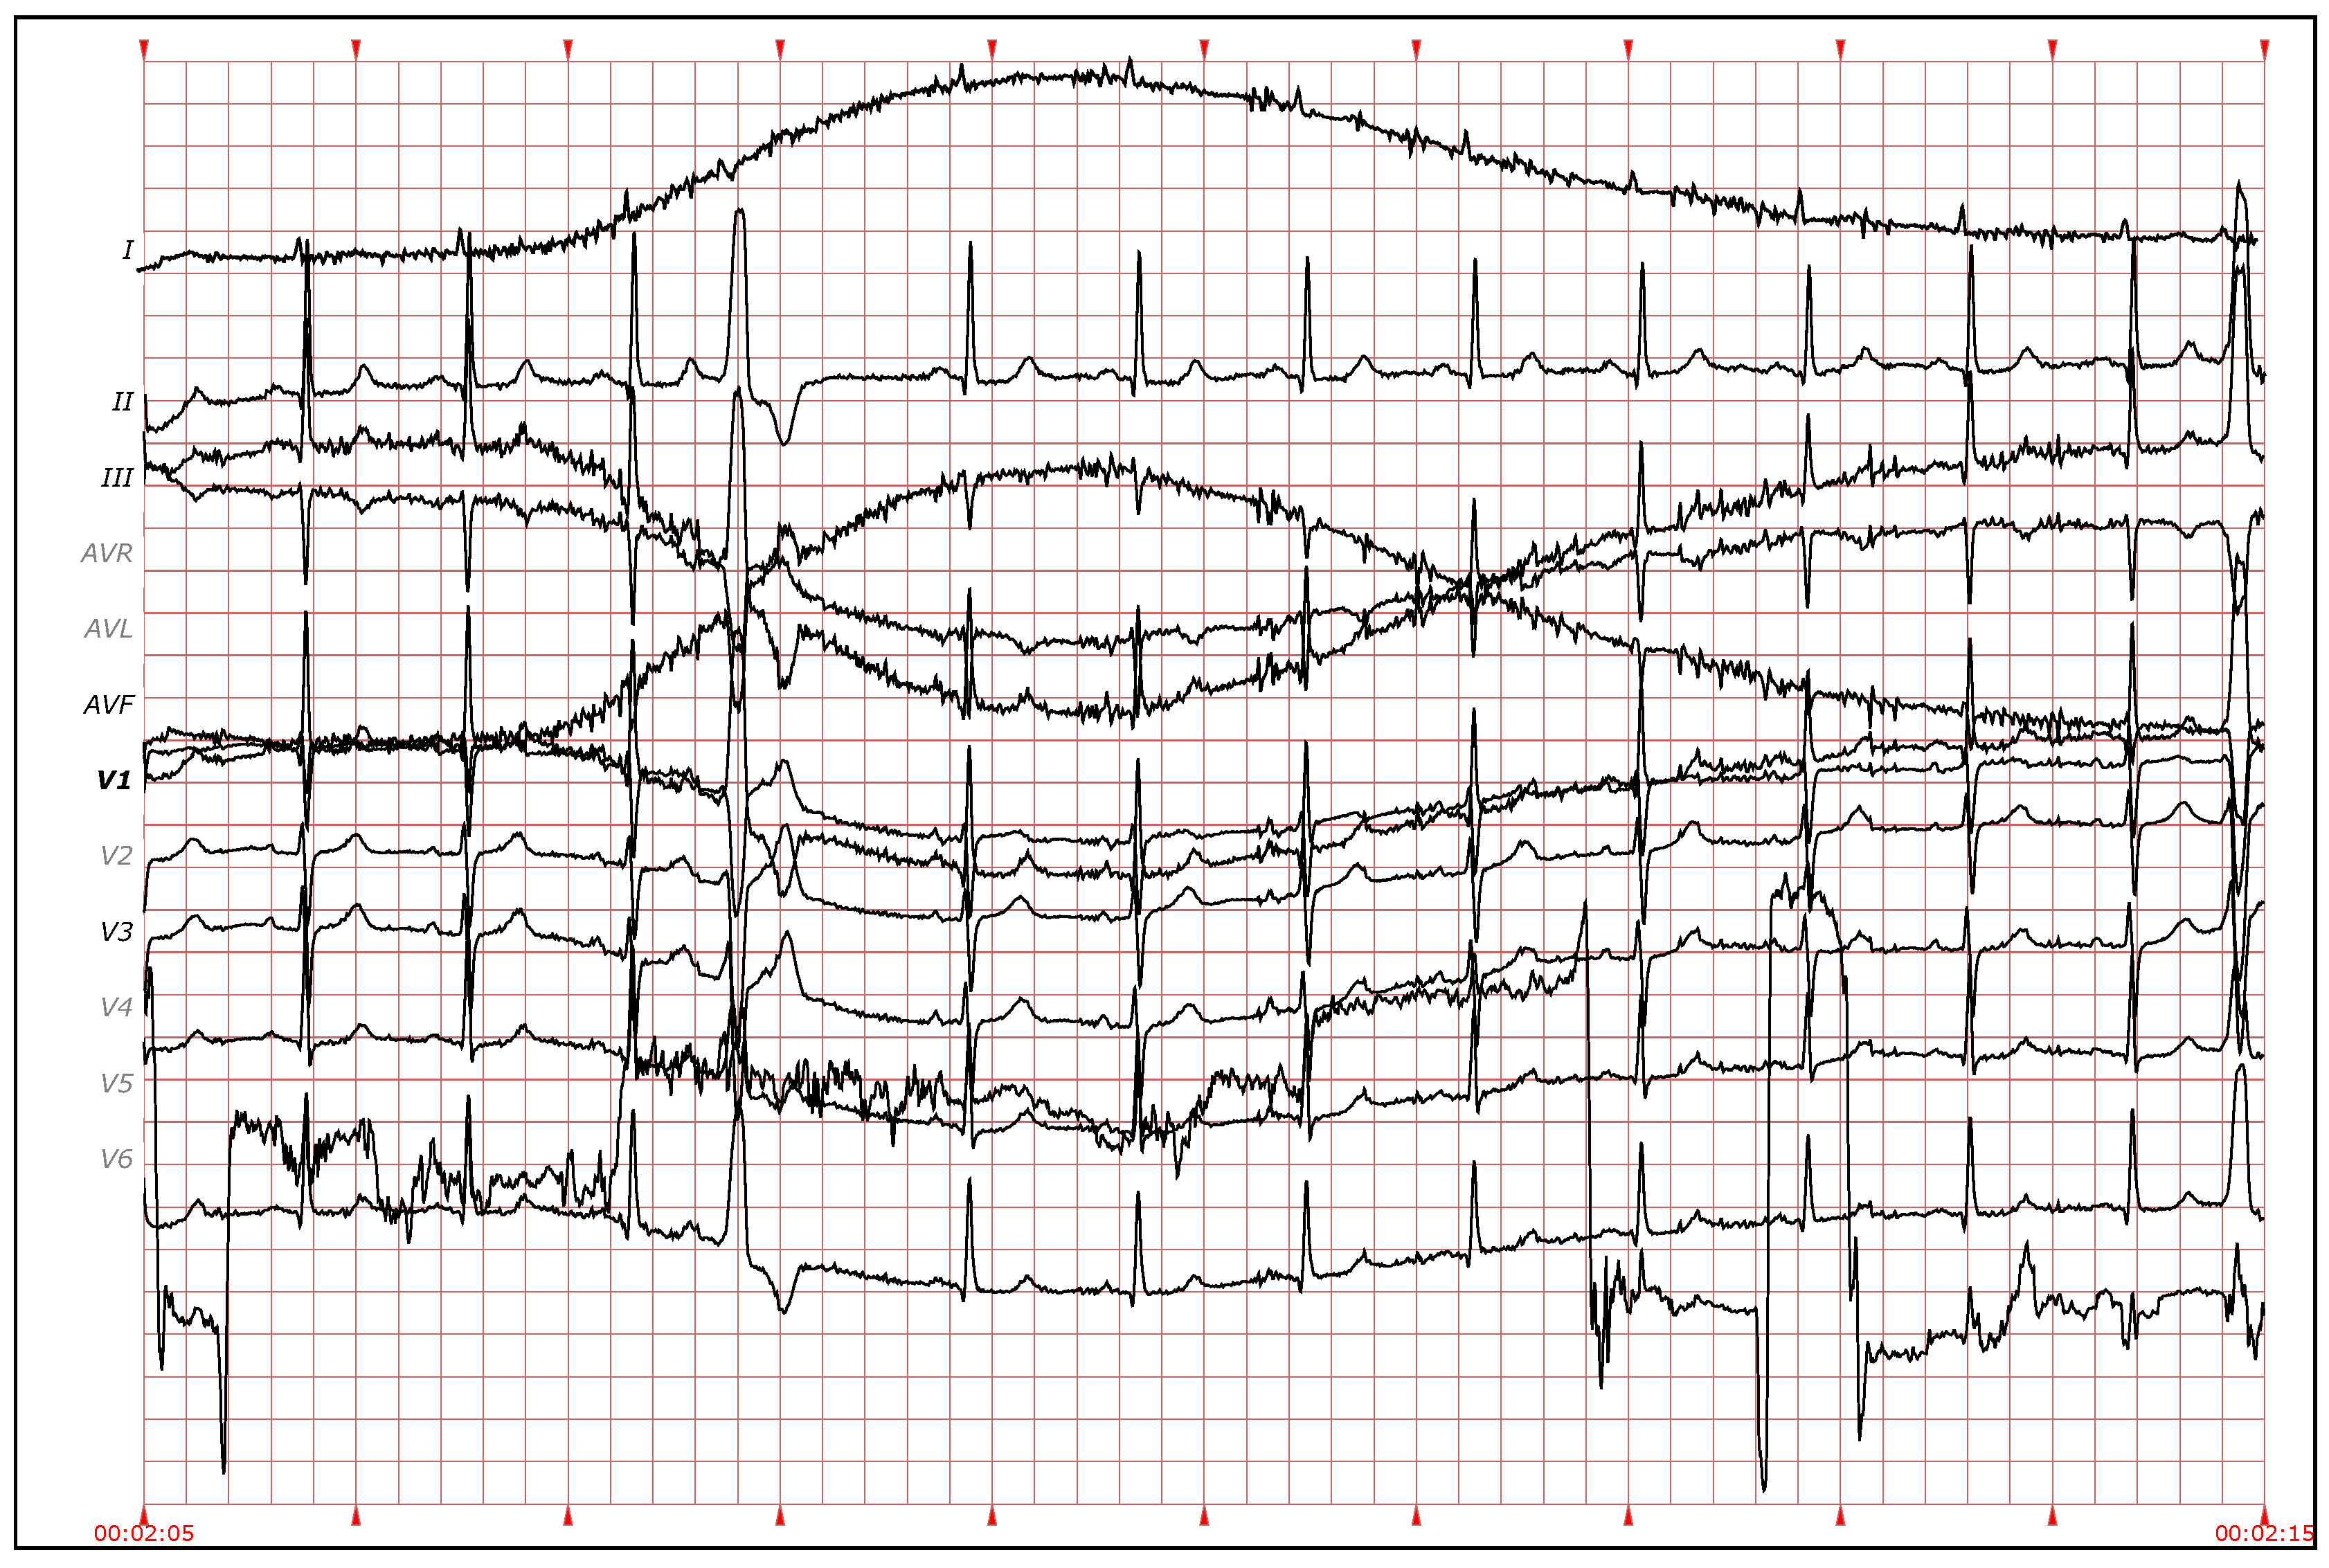

There are some types of arrhythmia, like premature atrial contractions and atrioventricular, or fusion and escape beats, in which the morphology of the QRS complexes is similar. Therefore, it is not feasible to distinguish between them using just QRS morphology information (see Figure 8 and Figure 9). The P wave does provide relevant information in these cases, but the difficulty in identifying it, especially in ambulatory ECG, often leads to attempts to obtain similar information from the distance between heartbeats [13,42]. Therefore, to allow the clustering algorithm to distinguish between different types of heartbeats with similar QRS morphology, two features based on the distance between heartbeats ( and ) were added as follows:

Figure 9.

Electrocardiogram (ECG) fragment with Nodal premature beats (J) at the beginning. Around the middle of the fragment, the distance between heartbeats increases and normal beats appear. (Source: MIT-BIH Arrhythmia Database, recording 234, from 0:14:27 to 0:14:37).